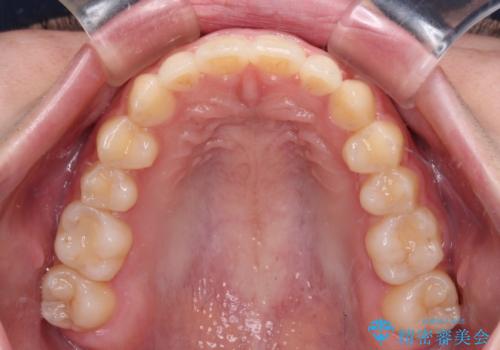

気になる残存乳歯と八重歯 ワイヤー矯正を併用したインビザライン治療

- 八重歯を気にして来院された患者様です。

八重歯のために乳歯が残存していたため、乳歯を抜去して八重歯となっている犬歯を歯列に収めることとしました。

八重歯の移動量が多くなるため、インビザラインと併用してワイヤー矯正を行い、八重歯を改善した後に、上下歯列をインビザラインで整えることとしました。

犬歯は歯根が長くて太いため移動に時間がかかる上に、周囲の歯が八重歯に寄ってきてしまうため、仕上がるまでに期間がかかりました。